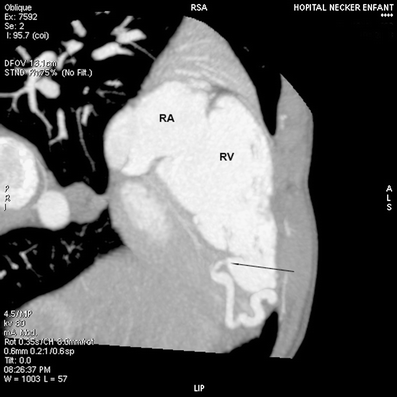

Oblique reconstruction through the right ventricle with maximal intensity projection. Note the direct fistula (arrow) between the distal segment of the left anterior descending artery and the apex of right ventricle (RA right atrium RV right ventricle)